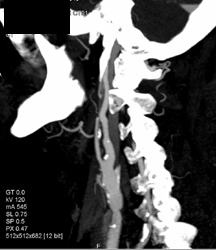

DIEP Protocol Study